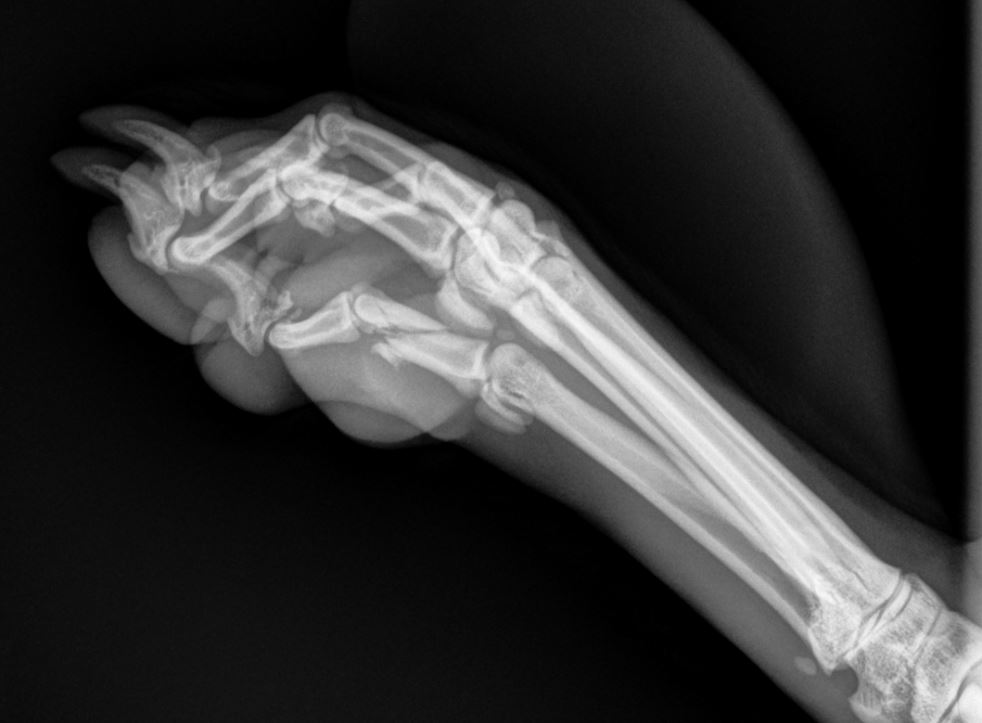

What To Expect With Dog XRays And Other Useful Info I Love Veterinary Does A Dog Need To Be Sedated For X Rays If your pet was sedated for the procedure, they may have decreased energy level or appetite after their appointment. If contrast was given by mouth, you may notice discoloration of the stool (often white, from barium). We sometimes need to sedate animals to ensure they remain both still and compliant. Only dogs free from hd are permitted for breeding. Does A Dog Need To Be Sedated For X Rays.